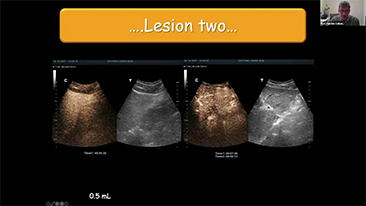

Jak wyra?nie mo?na zobaczy? w?trob??

W przypadku ogniskowych zmian w w?trobie, takich jak naczyniaki czy nowotw├│r w?troby, obrazowanie USG z kontrastem odgrywa wa?n? rol?. Technologia obrazowania USG z kontrastem UWN+ mo?e pom├│c uzyska? lepsz? penetracj?, lepsz? jako?? obrazu z ni?szym indeksem mechanicznym MI oraz d?u?szy obserwowany czas perfuzji.